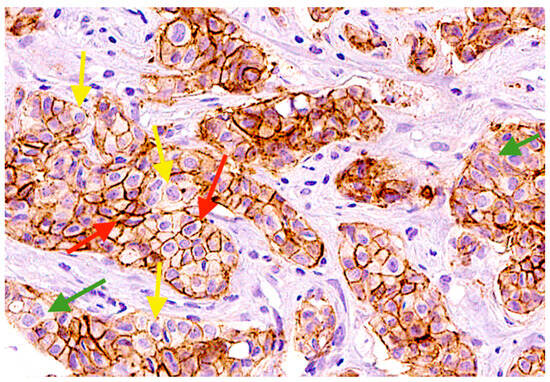

2.4. EpCAMhigh, EpCAMlow, and EpCAM-Negative Tumor Cells in Primary Tumor of BC Patients